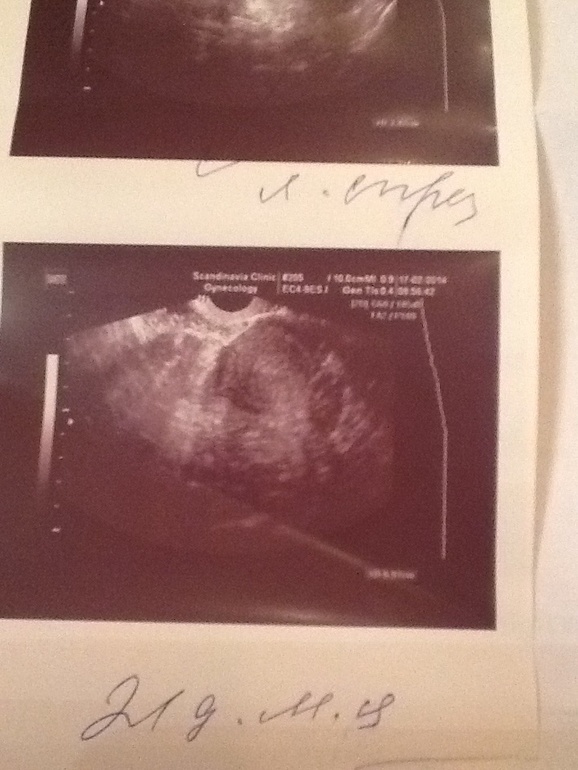

Оль на узи былобы видно жетое тело после разрыва фоликула это еслиб О была, еслиб ее не было но намечалась то былобы видно зреющие фоликулы. К сожалению я не вижу не того ни дркгуго, есть сто-то похожее на зреющий фоликул в левом яичнике, но он настолько нечетки что скорее всего он и не развивался(( похоже что о не было и не будет(((

Оля а в узи заключении что-то написано?

В том то и дело,что нет,там в кабинете у г стоит мини аппарат узи,она по нему смотрит,руками не смотрела вообще,но так как у меня стоит СПКЯ,видимо это не обсуждается,что вдруг может быть б(так обидно..по ощущениям и яб сегодня 5-6 дпо..